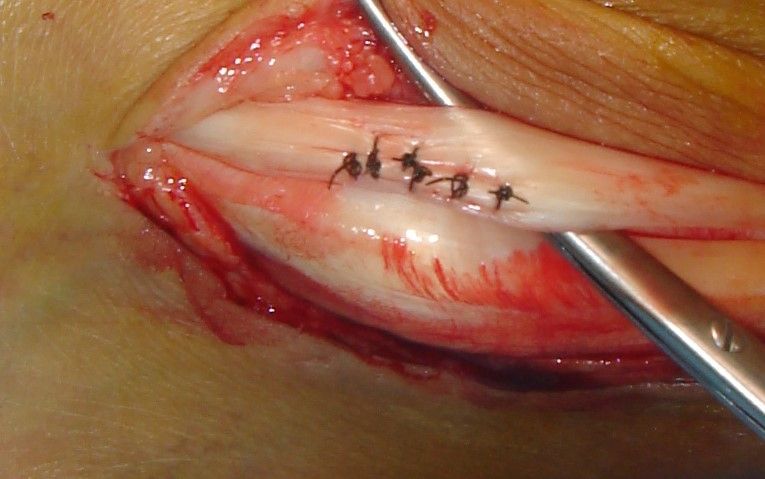

1. Ηallux valgus of the right foot in a 28-year-old female.

Treatment: Scarf osteotomy of the first metatarsal